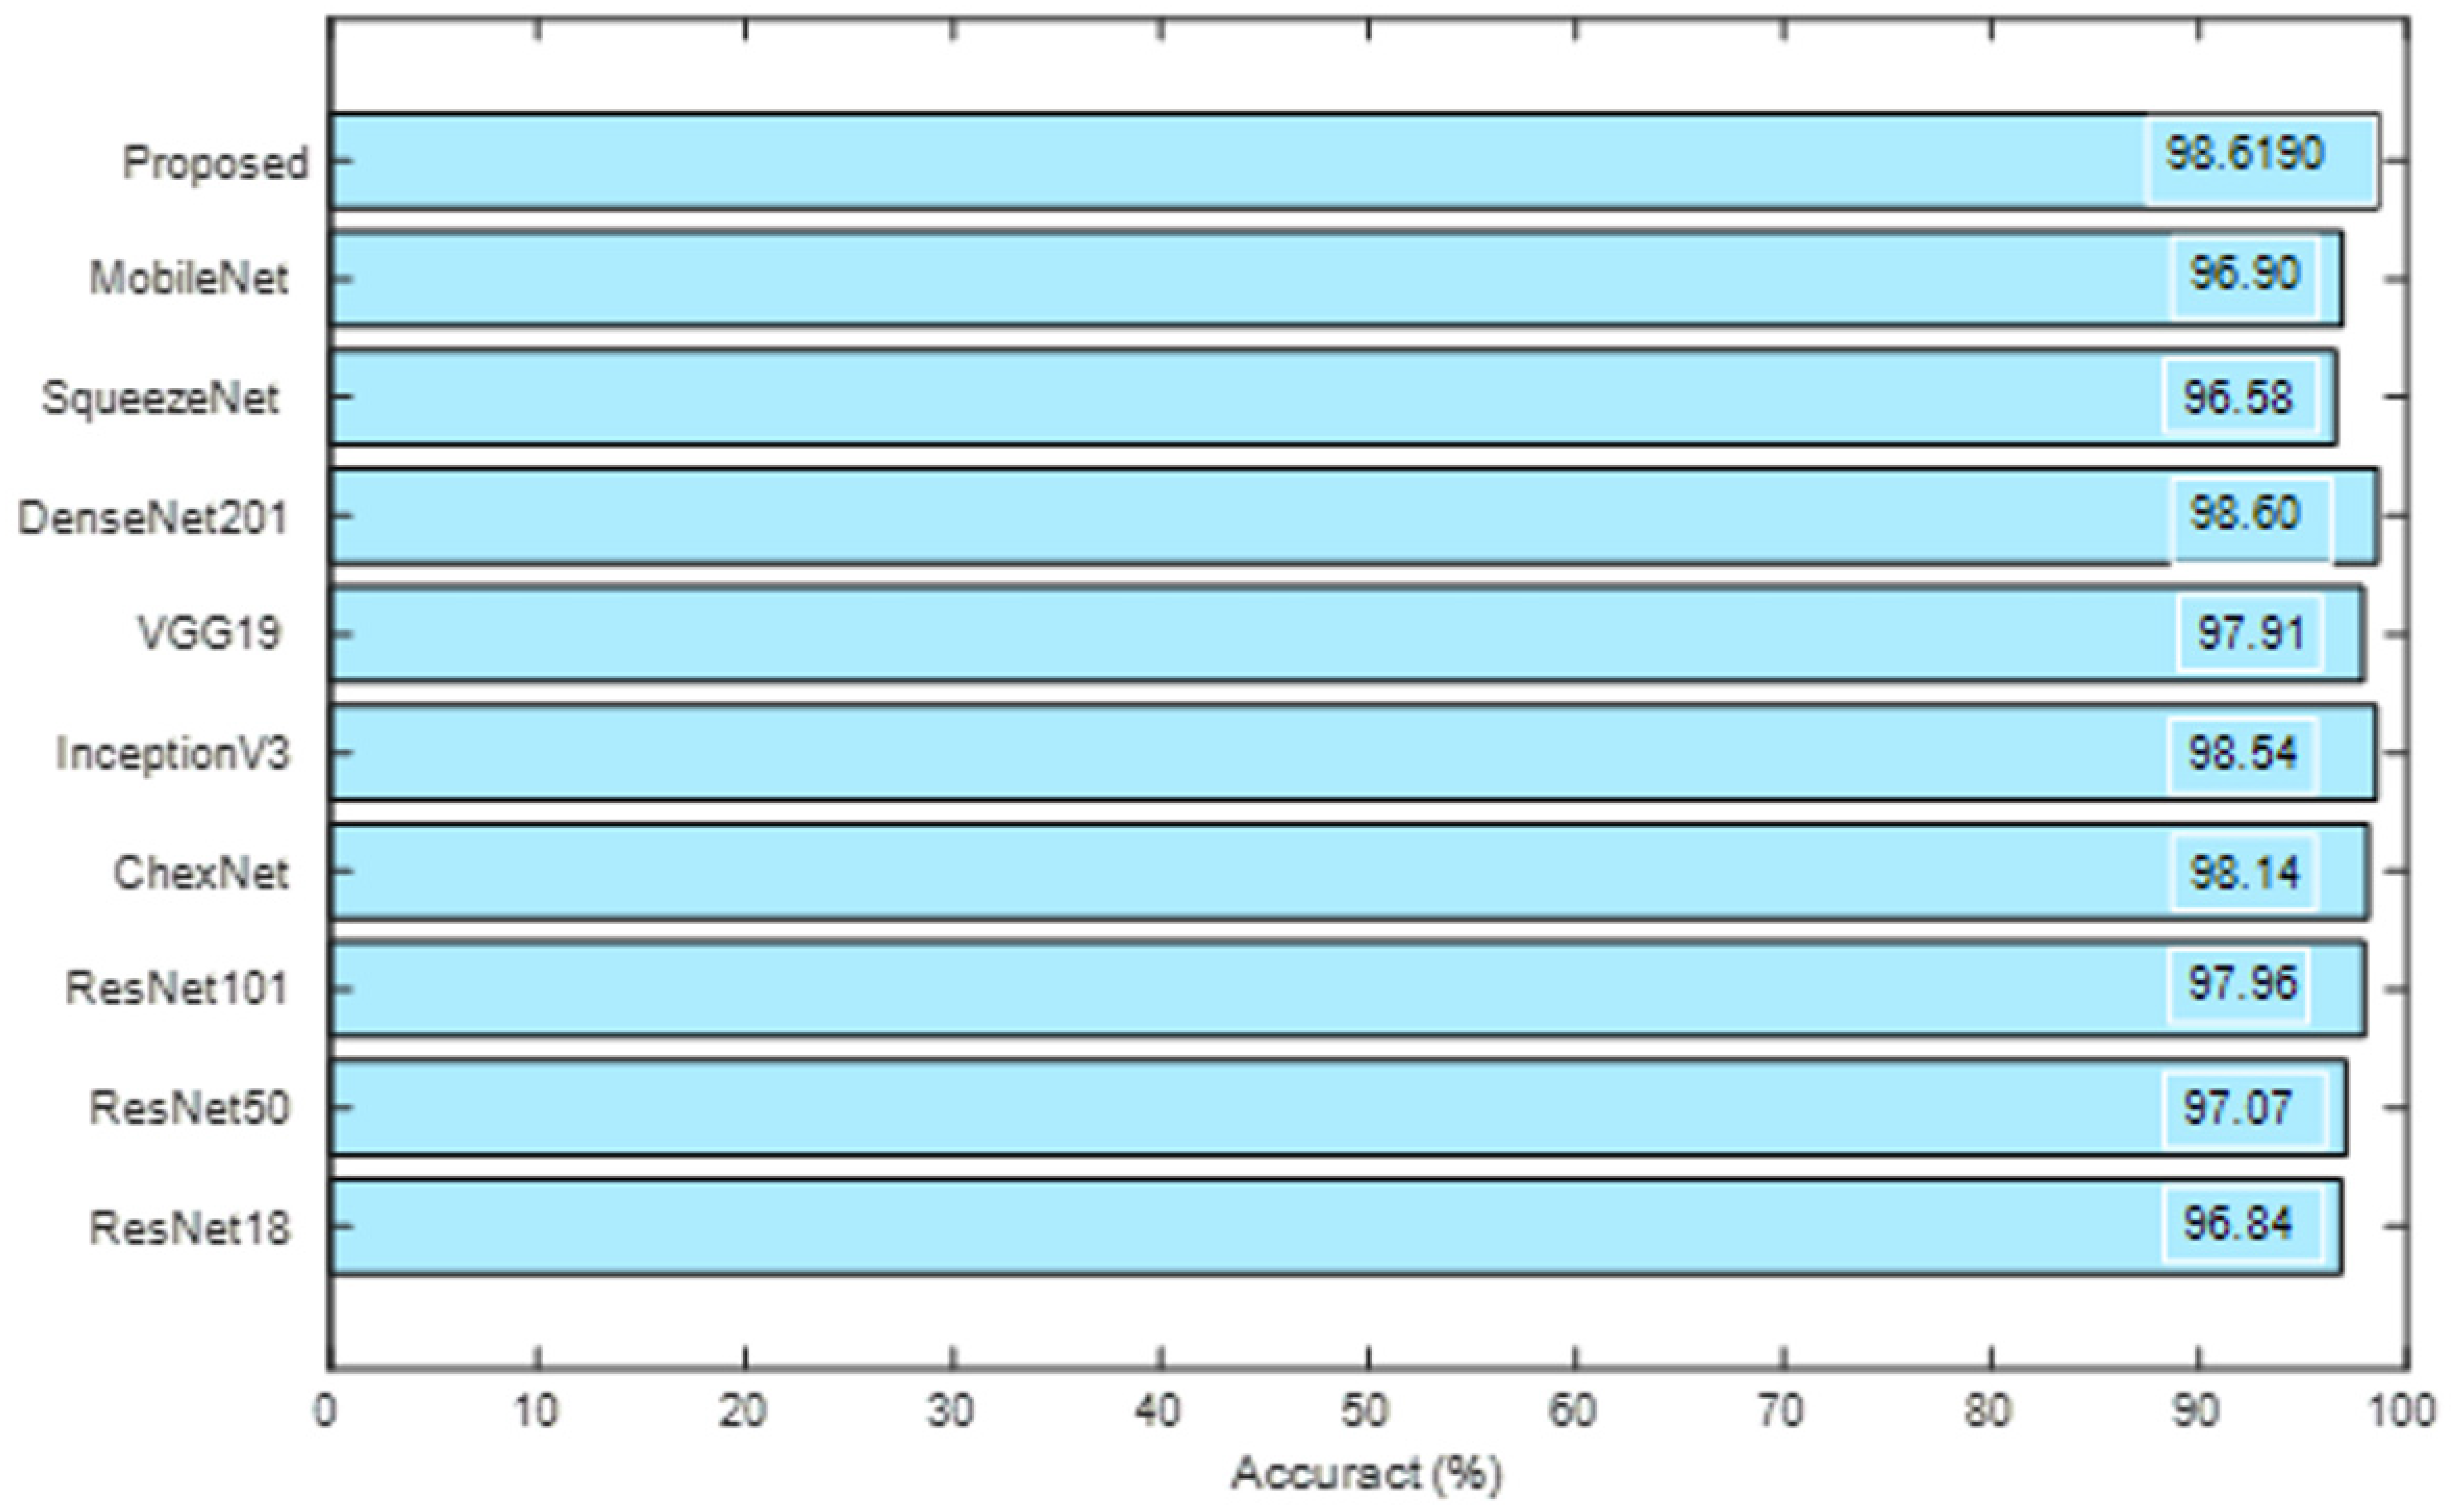

| Rahman et al. [18] | This work employed Conv Neural Network (CNN) supported joint segmentation and classification to classify 7000 number of test images into healthy/TB class. With the proposed technique, this scheme achieved a best classification accuracy of 96.47% (without segmentation) and 98.6% (with segmentation), respectively. |

| VGG19 | 979 | 71 | 972 | 78 | 92.9048 | 92.6206 | 93.2381 | 92.5714 | 93.1927 |

| VGG16 | 966 | 84 | 966 | 84 | 92.0000 | 92.0000 | 92.0000 | 92.0000 | 92.0000 |

| AlexNet | 962 | 88 | 955 | 95 | 91.2857 | 91.0123 | 91.6190 | 90.9524 | 91.5628 |

| ResNet101 | 956 | 94 | 971 | 79 | 91.7619 | 92.3671 | 91.0476 | 92.4762 | 91.1737 |

| ResNet50 | 958 | 92 | 947 | 103 | 90.7143 | 90.2922 | 91.2381 | 90.1905 | 91.1453 |

| ResNet18 | 960 | 90 | 948 | 102 | 90.8571 | 90.3955 | 91.4286 | 90.2857 | 91.3295 |

| Inception-v3 | 951 | 99 | 957 | 93 | 90.8571 | 91.0920 | 90.5714 | 91.1429 | 90.6250 |

| SVM-Medium Gaussian | 1029 | 21 | 1042 | 8 | 98.6190 | 99.2285 | 98.0000 | 99.2381 | 98.0245 |